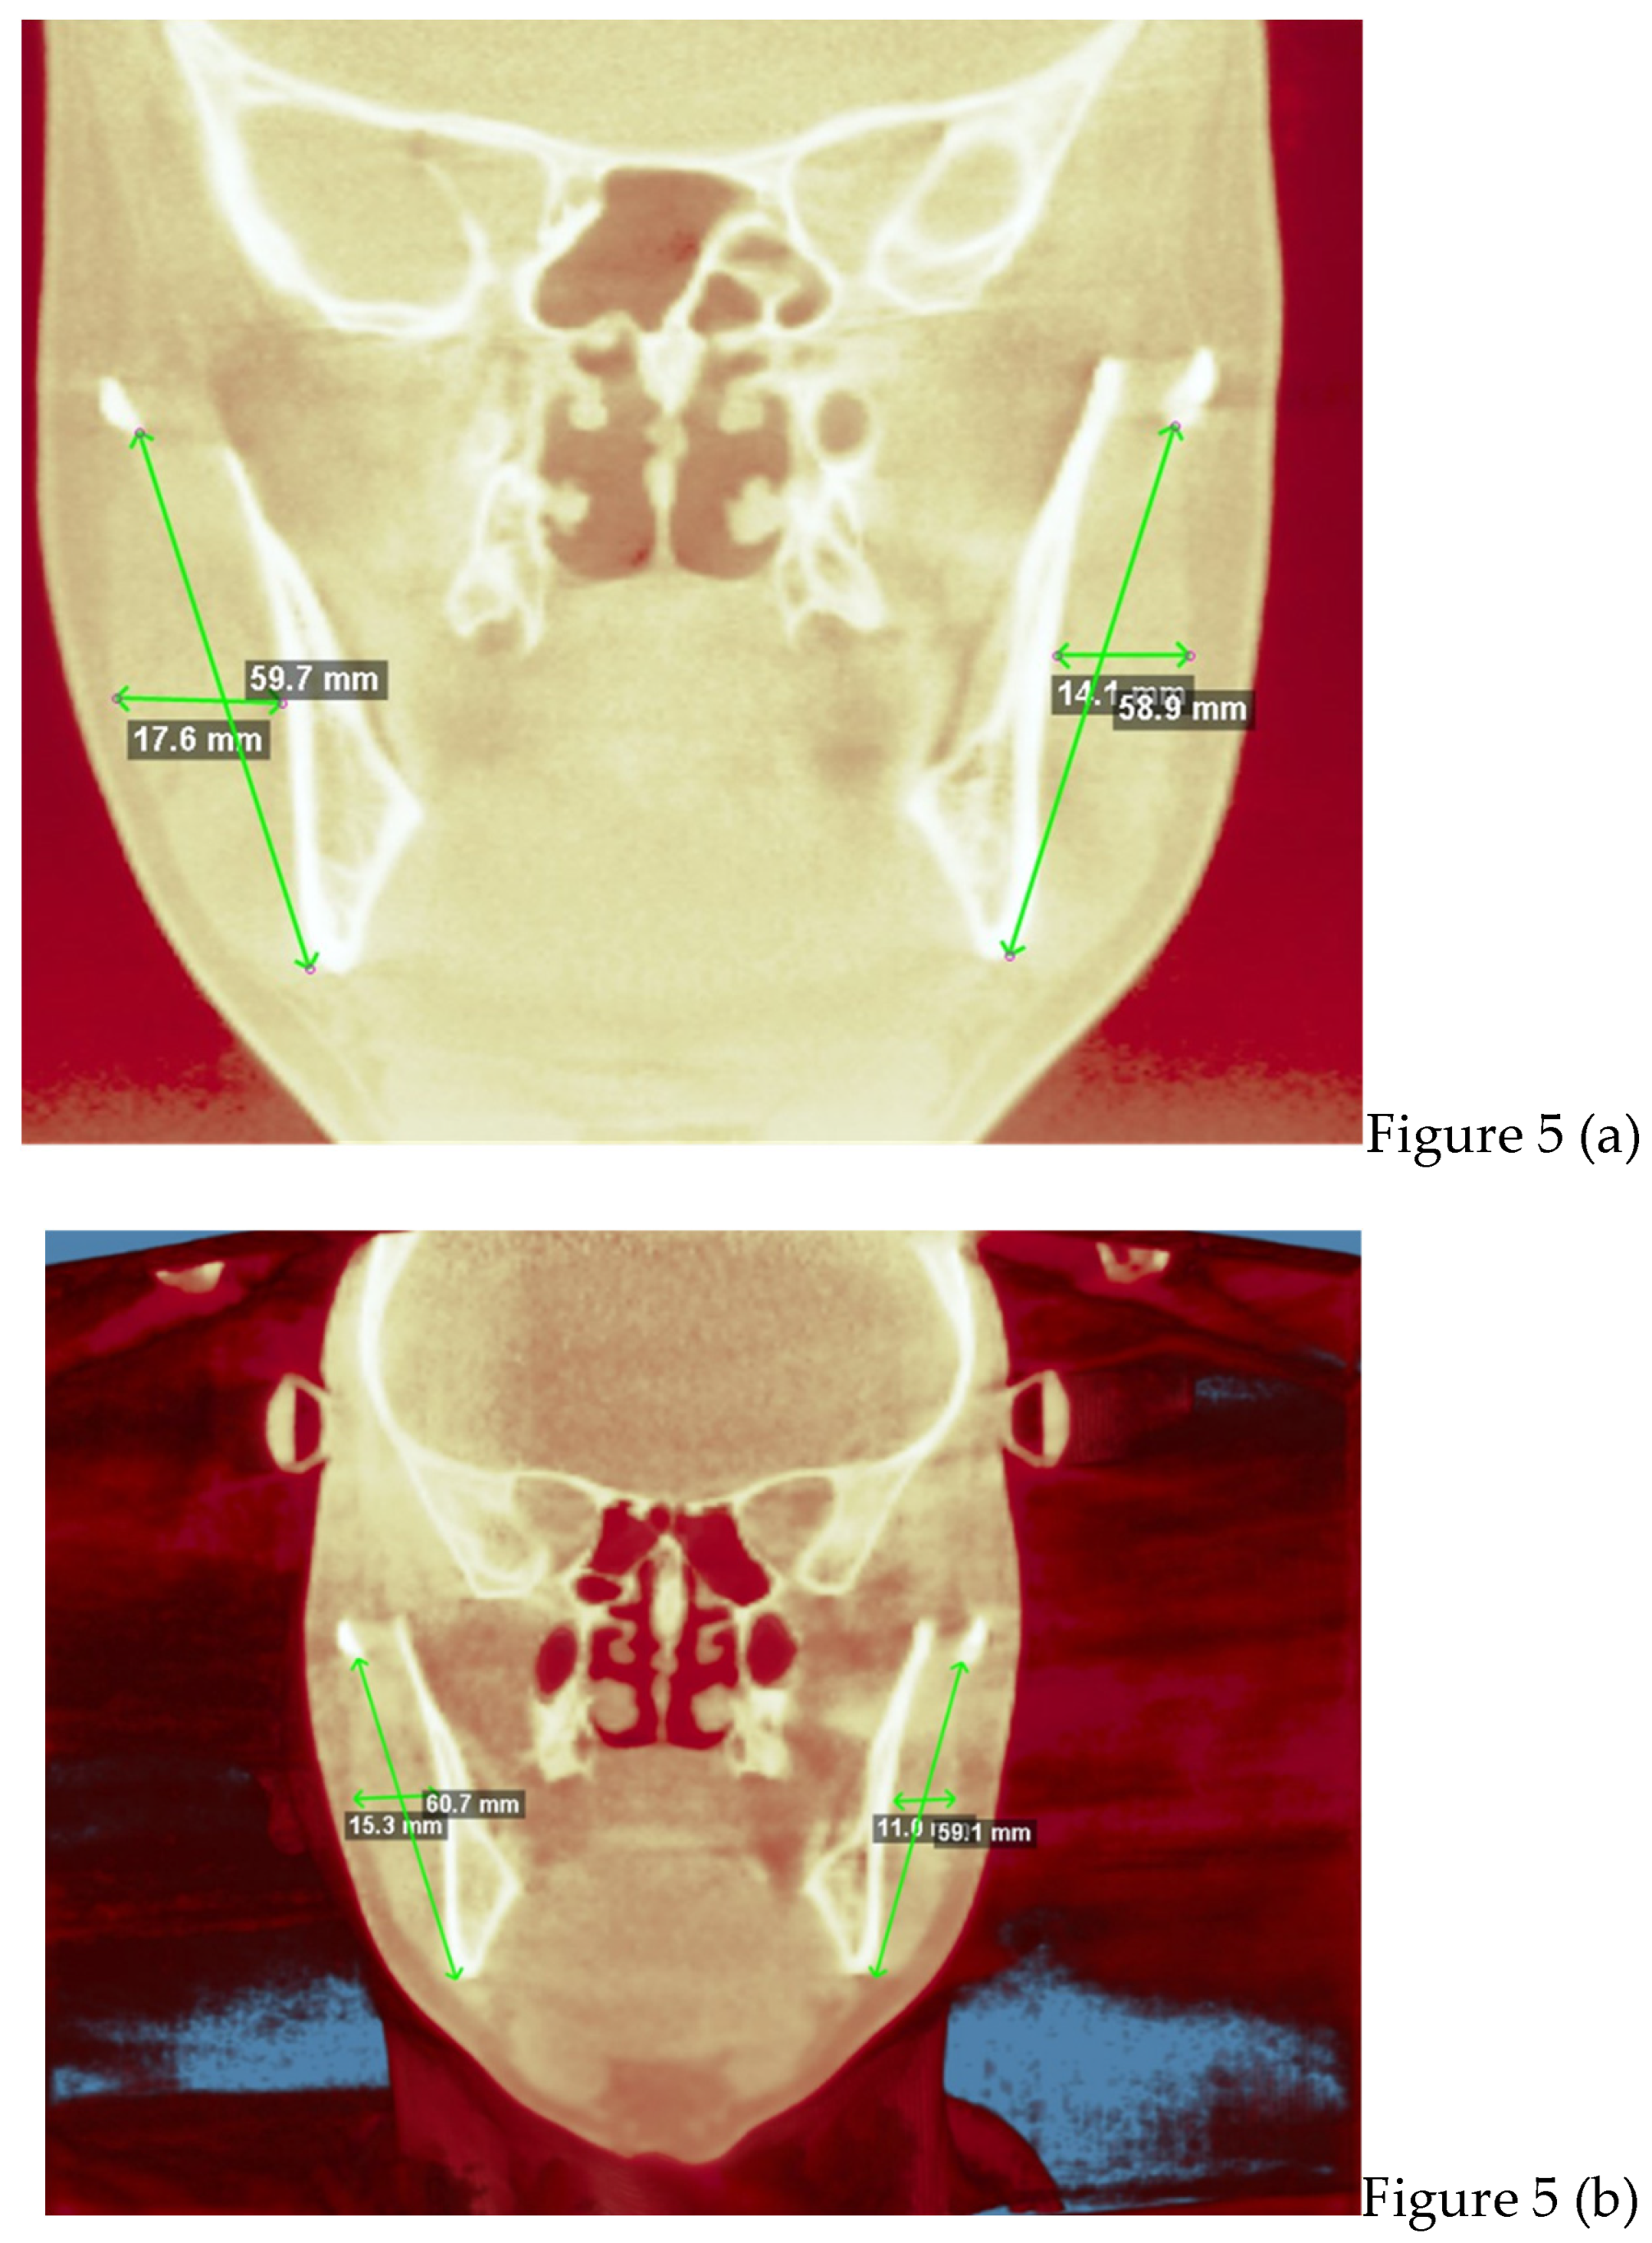

2.2. Cone Beam CT Analysis